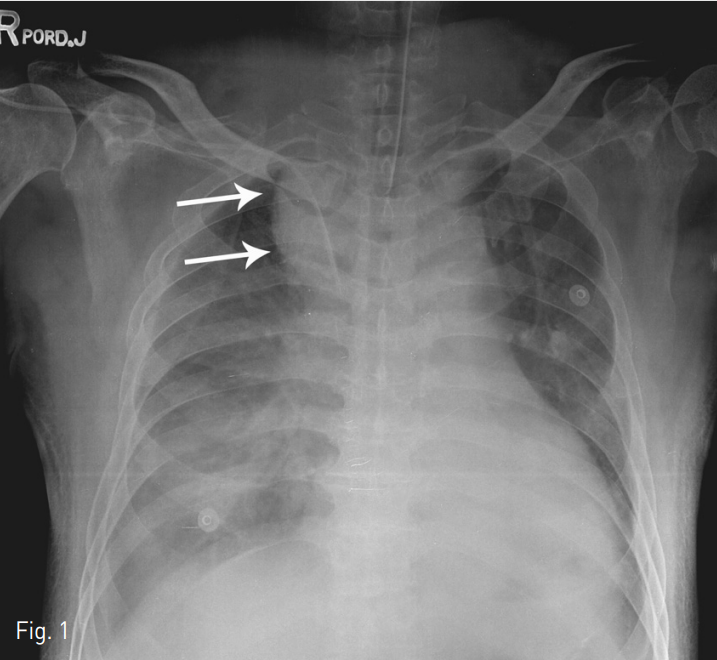

단순 X-ray촬영상 기관지 우측으로 확장된 음영이 관찰되었고 (Fig. 1) CT 검사상 우측 척추동맥에서 발생된 큰 가성동맥류가 관찰되고 (Fig. 2) 우측 종격동내에는 다량의 혈종이 보였다.

Fig. 1

Plain chest x-ray showing the bulging contour of right paratracheal area (arrows) and supra-mediastinal widening.